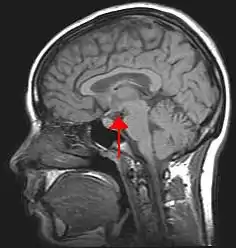

Brain imaging involves analyzing activity within the brain while performing various tasks. This allows us to link behavior and brain function to help understand how information is processed. Different types of imaging techniques vary in their temporal (time-based) and spatial (location-based) resolution. Brain imaging is often used in cognitive neuroscience.